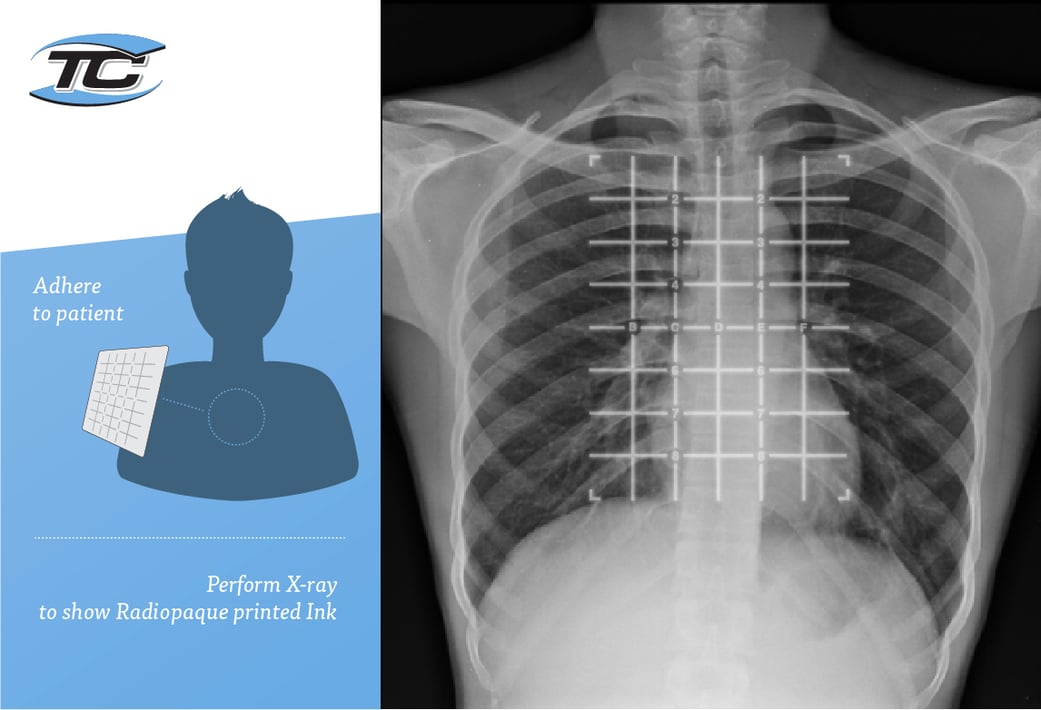

From www.tapecon.com

Radiopaque Markers How Do Radiopaque Markers Work More precise testing and clearer information can reduce the number of radiographic tests a patient is subjected to, or help make surgical procedures less invasive. How radiopaque markers enhance imaging clarity. Radiopaque markers have revolutionized medical imaging, providing greater clarity in diagnostic. Radiographers are taught from day one in school to place radiopaque anatomical markers within the primary. In medical. How Do Radiopaque Markers Work.

Radiopaque Markers How Do Radiopaque Markers Work How radiopaque markers enhance imaging clarity. More precise testing and clearer information can reduce the number of radiographic tests a patient is subjected to, or help make surgical procedures less invasive. Radiopaque markers have revolutionized medical imaging, providing greater clarity in diagnostic. Radiopaque agents are drugs used to help diagnose certain medical problems. In medical imaging, radiopaque materials are used. How Do Radiopaque Markers Work.

Radiopaque marker on chest radiograph Download Scientific Diagram How Do Radiopaque Markers Work More precise testing and clearer information can reduce the number of radiographic tests a patient is subjected to, or help make surgical procedures less invasive. Help quickly identify the location of nipples as a point of reference for measurements, proper positioning, and comparative image. In medical imaging, radiopaque materials are used to enhance the visualization of organs, tissues, blood vessels,. How Do Radiopaque Markers Work.